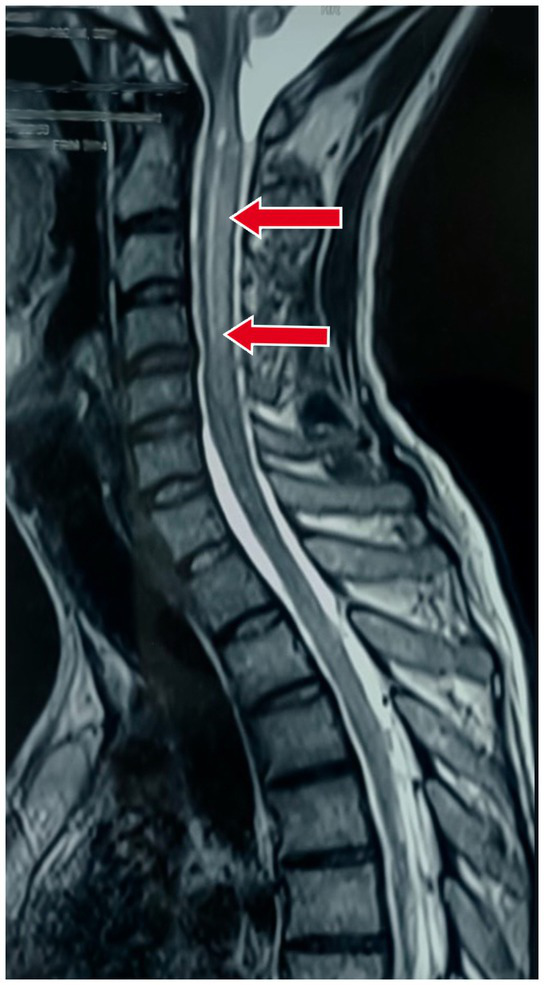

Also, an MRI of the cervical spine with whole spine screening was performed to rule out the cause of the quadriparesis. This revealed longitudinal, extensive midline hyperintense lesions on T2-weighted imaging in both the upper and lower cervical spinal cord, suggestive of long-segment cervical cord myelitis with associated cord oedema as shown in Figure 2.

Magnetic resonance imaging (MRI) of the cervical spine in the sagittal section showing longitudinal extensive midline hyperintense lesions on T2-weighted imaging in both the upper and lower cervical spinal cord, suggestive of long-segment cervical cord myelitis with associated cord oedema.

| 3. Investigations | MRI of the brain: Meningeal enhancement with extraventricular obstructive hydrocephalus with hyperintense debris on the basal cisterna (Figures 1A–H) MRI of the cervical spine: Longitudinal extensive hyperintense lesions predominantly in the upper cervical and the lower cervical regions (Figure 2). CSF analysis: Cobweb appearance with elevated pressure, proteins, and cells (predominantly lymphocytes) with positive CBNAAT and raised ADA (Table 1). Chest X-ray: Multiple homogeneous small nodular opacities are present in both lung fields suggesting miliary mottling (Figure 3A) HRCT thorax: Snowstorm appearance of miliary mottling (Figure 3B) Sputum examination: Acid-fast bacilli (AFB) grade-III growth on direct Ziehl Neelsen (ZN) stain microscopy (Figure 4). Routine investigations: Within normal limits with non-reactive tests for HIV, hepatitis B, and hepatitis C. Autoimmune profile: Negative ANA with negative for NMOSD and multiple sclerosis. |

MRI remains the gold standard for diagnosing meningeal and spinal cord involvement in tuberculosis. In this patient, MRI findings of diffuse meningeal enhancement and longitudinal spinal cord lesions were crucial in establishing the diagnosis (8). Additionally, high-resolution computed tomography (CT) of the thorax revealed a miliary pattern, indicating disseminated TB, which further supported the likelihood of CNS involvement.